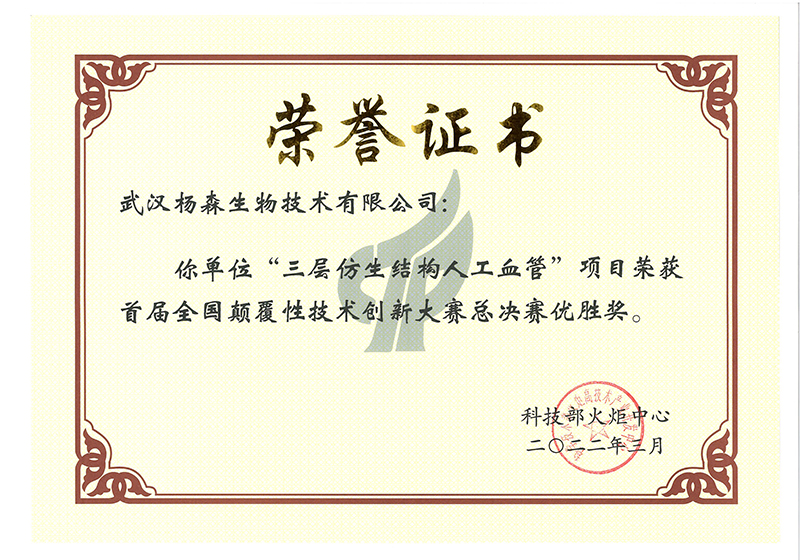

jinnian金年会成立于2009年4月,是集团旗下专业从事高端医疗器械研发、生产与销售的国家高新技术企业,坐落于国家级生物产业基地-武汉光谷生物城。现拥有1000m²符合GMP要求的万级洁净厂房;授权和受理国内外发明专利近20项;2017、2018年连续两年承担国家重点研发计划项目。